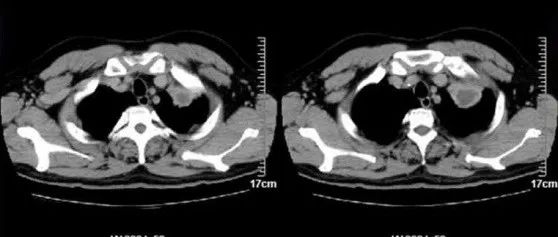

肺脓肿是由于多种病因所引起的肺组织化脓性病变。早期为化脓性炎症,继而坏死形成脓肿。现介绍宾夕法尼亚大学的 James X. Chen 医生在 auntminnie 上发布的一个因上肢蜂窝织炎导致肺脓肿的病例。病史27 岁女性,发热、气短,两天前因右上肢蜂窝织炎和坏死性筋膜炎并发血栓性静脉炎而接受筋膜切开术和组织瓣重建术。影像学检查及发现图 1 为肺动脉 CTA 肺窗,可见双侧中量胸腔积液(红色箭头)...